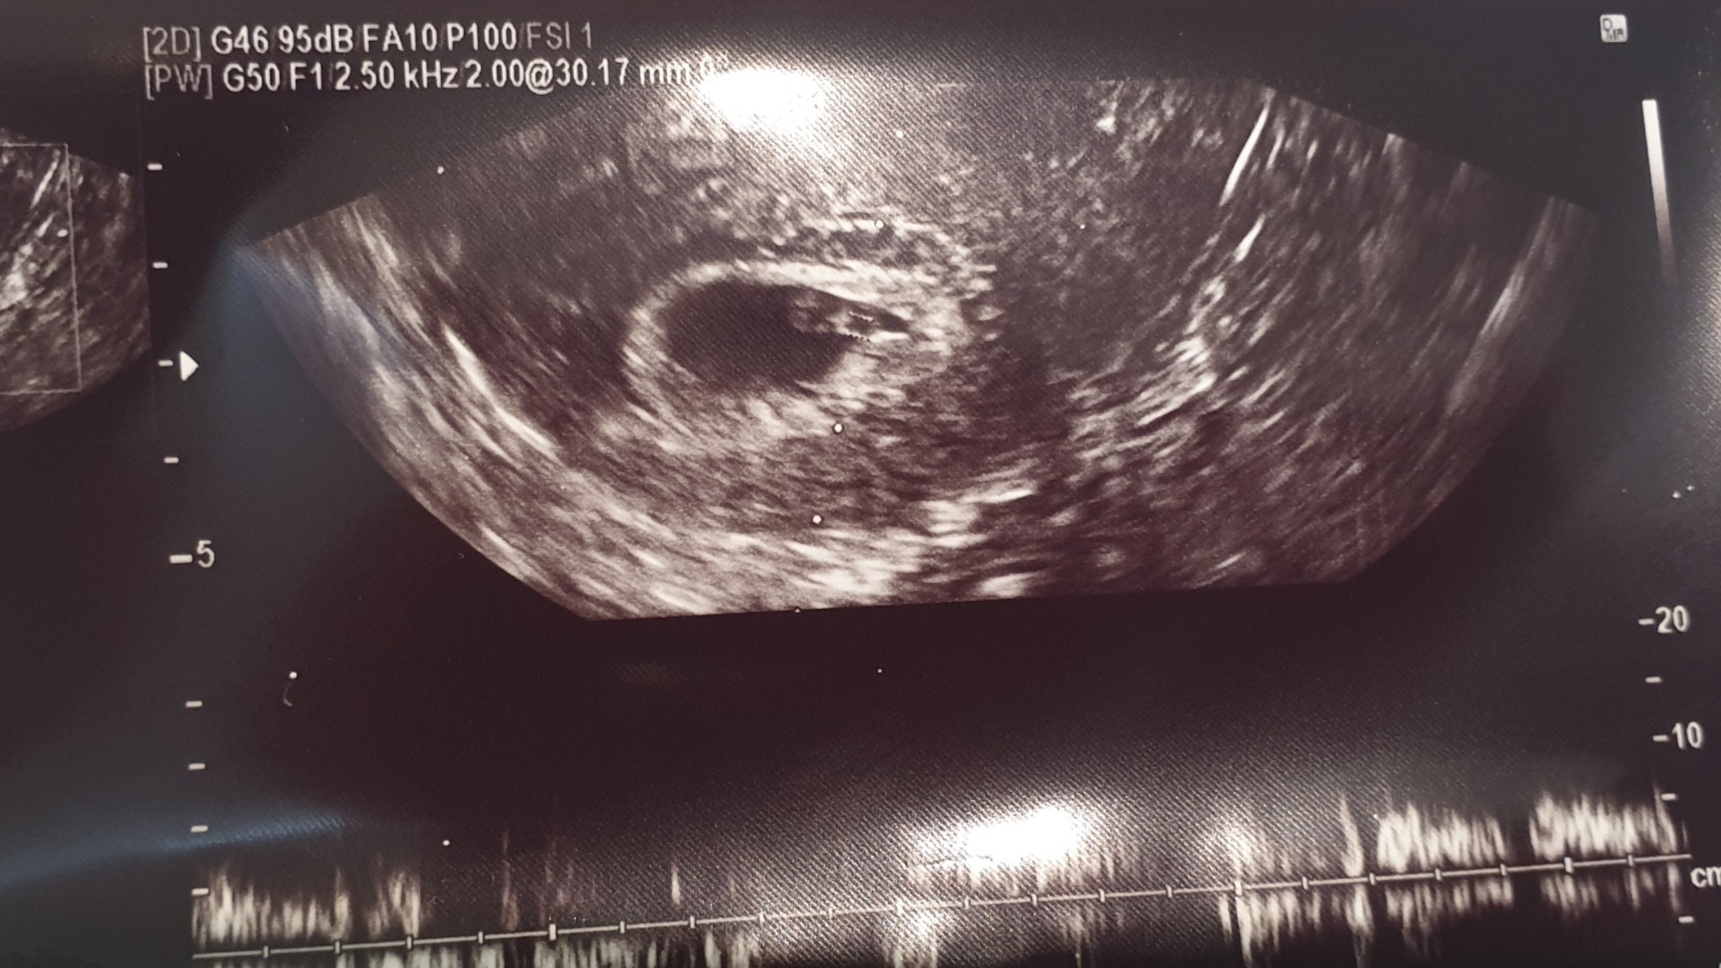

임신 12주차 엄마 배속안의 아기천사입니다.

아름다운 소리. 숨쉬는 그 소리.

세상에서 가장 행복한 소리 한번 들어보셨으면 합니다.

세상의 빛을 보진 않았지만. 아니 못했지만....

엄마의 뱃속에서 요동치는 아이의 심장소리.

어느 뱃고동 소리보다 크게 들리며.

세상에서 가장 아름답고 좋은 소리이지 않을까??